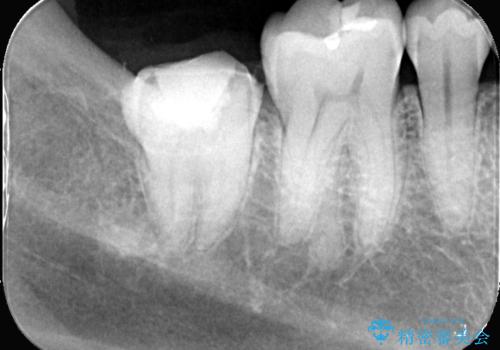

- 頬側に大きな虫歯があり、神経に達している可能性が高かったため、虫歯除去時に神経が出た場合はVPTを提案しました。

虫歯が神経まで達していましたが、術前の検査でVPTの適応と診断をしていたので、ラバーダムシートを装着しVPTを行いました。

経過も良好で、痛みも無く神経を残すことが出来ました。